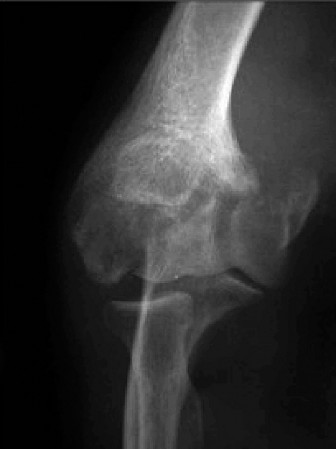

Physicians should obtain a complete set of x-rays. Special views include the modified Westpoint axillary (Fig. 2–43B) to evaluate for glenoid loss and the stryker notch view (Fig. 2–43A) to evaluate the Hill–Sachs lesion. This view brings the posterolateral defect into direct visualization. 3D CT imaging is also very useful for evaluating glenoid bone loss and estimating the size of the Hill–Sachs lesion.

--- _Figure 2–43_A: Stryker notch view. B: West point axillary view. (From Bucholz RW and Heckman JD. Rockwood and Green’s Fractures in Adults 7e. Philadelphia: Wolters Kluwer, 2009.)